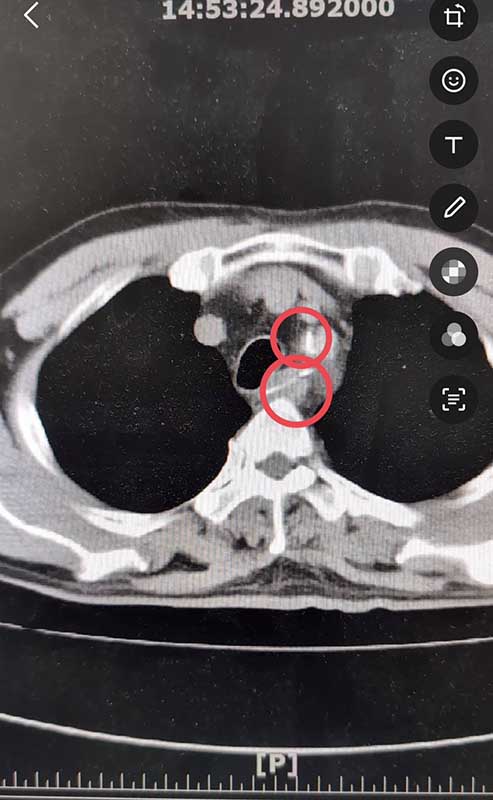

到急診室時因為主訴胸痛,血壓又偏高(收縮壓約170、舒張壓約95),急診團隊為他進行抽血、照心電圖、胸部x光、斷層掃描等檢查,想逐一排除心肌梗塞與主動脈剝離的可能性,結果在斷層掃描片子中赫然發現食道內有兩根長約三公分的異物,經會診腸胃科王允成醫師進行內視鏡檢查,竟然夾出兩根長約三公分、如五十元銅板大小的魚刺。